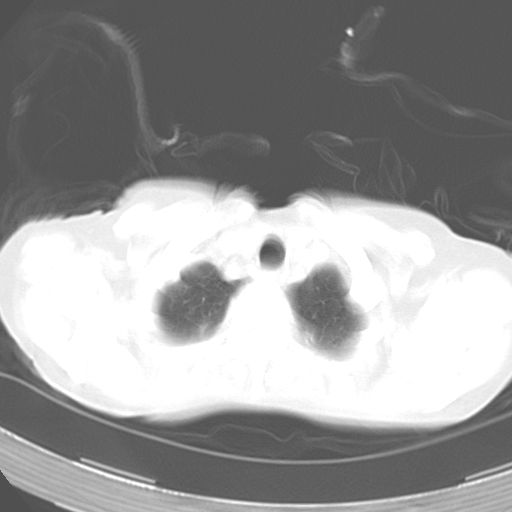

以下是引用dyqct在2006-12-7 21:08:00的发言:[br]考虑:1、肝内外胆管多发性结石伴肝左叶外侧段肝萎缩;[br] 2、右膈下多发脓肿;[br] 3、右侧少量胸腔积液、斜裂积液;[br] 4、左肾囊肿。

以下是引用jiazh在2006-12-7 20:37:00的发言:[br]肝脏周围半狐形低密度影,肝脏表面受压推移,考虑膈下脓肿可能性大;2、右侧胸腔积液

以下是引用拾荒者在2006-12-7 21:44:00的发言:[br]肝内外胆管多发结石,右膈下多发脓肿,右胸膜腔及叶间裂积液,左肾囊肿。[br] [br]